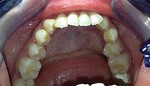

Paziente candidato a intervento di chirurgia Ortognatica